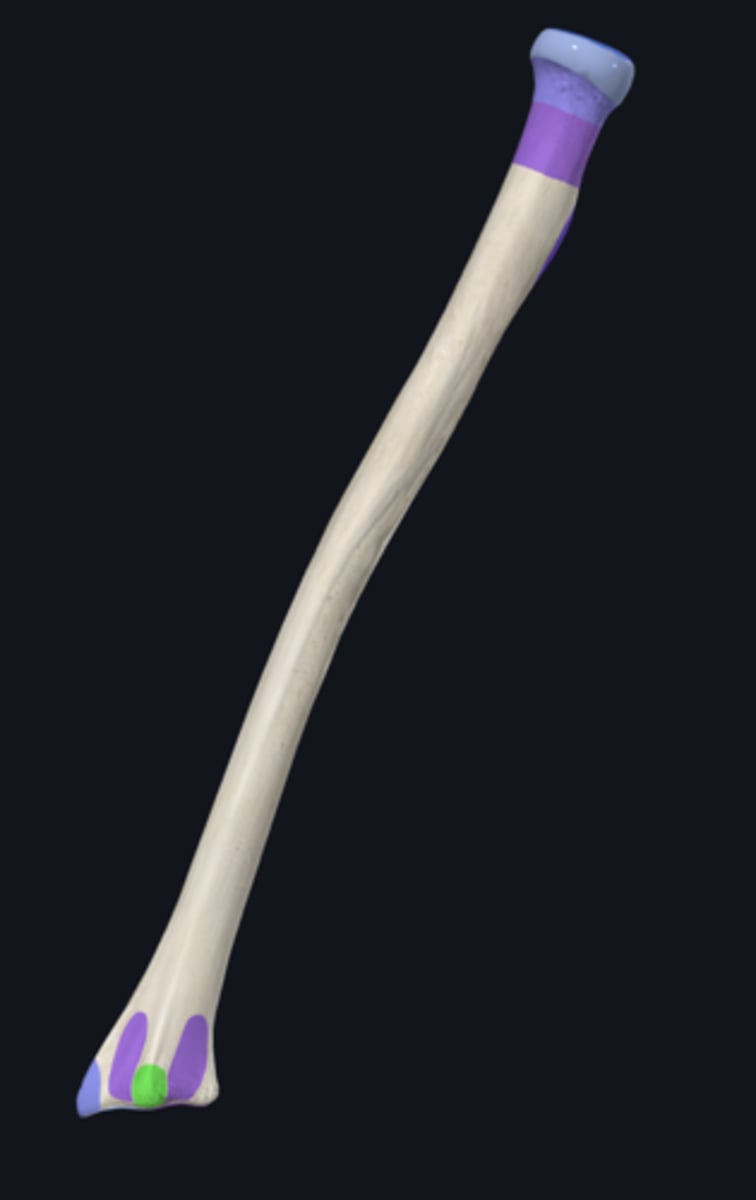

body of ulna

distal part of ulna

proximal part of ulna

anterior border of ulna

anterior surface of ulna

interosseous border of ulna

medial surface of ulna

posterior border of ulna

posterior surface of ulna

supinator crest

articular circumference of head of ulna

articular facet of head of ulna

coronoid process

head of ulna

olecranon process

radial notch

sublime tubercle

supinator fossa

trochlear notch

tuberosity of ulna

ulnar styloid process